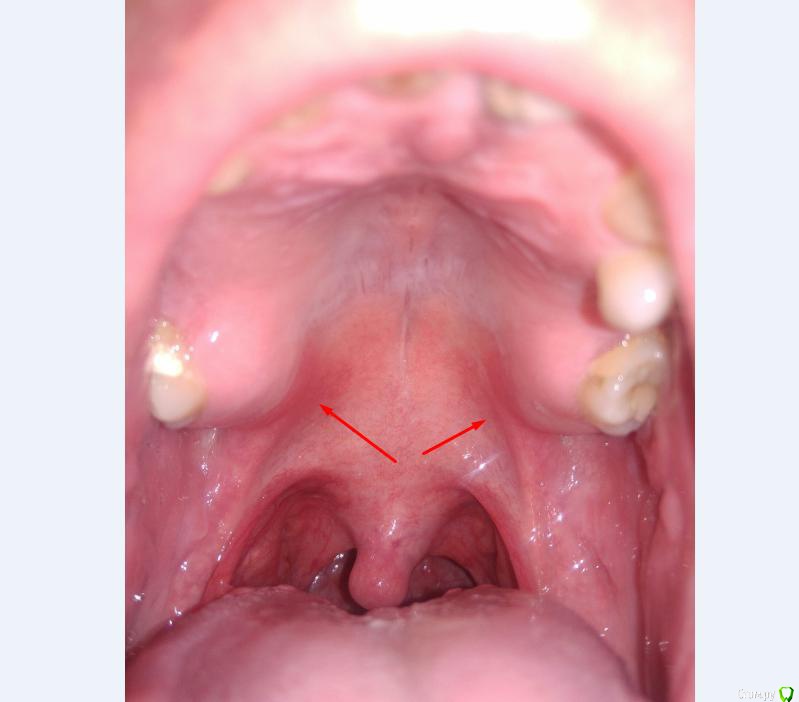

Лежал в больнице, все анализы ,узи, всё в норме. Чувствую воспалительный процесс где-то в  ротовой полости. Дёсна красные на краях, там где переходят в нёбо, особенно слева за 27 зубом. (на фото видно)

Просьба ко всем не равнодушным! Глянуть КТ верхней челюсти, 27 зуб  и место где удалили 16, может ещё где-то могут быть проблемы.  На фото видно где покраснение на дёснах, в этих местах возникают боли при движении головой. Бывает боль слева если засыпаю на левой стороне. Набуханий или флюсов нигде не видно.Прошу делиться мнениями, для меня это очень - очень важно. Стоматолог визуальных проблем на месте удалённого зуба не видит, всё зажило.